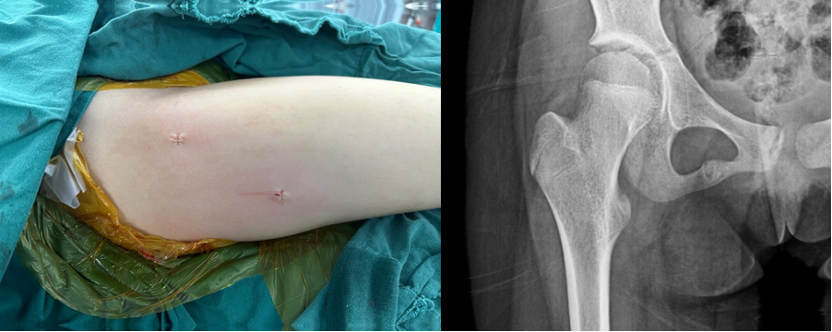

红:经皮射频消融穿刺点;黄:导航参考架置入点。

微创术后切口及术后X线片,术后病理示骨样骨瘤。